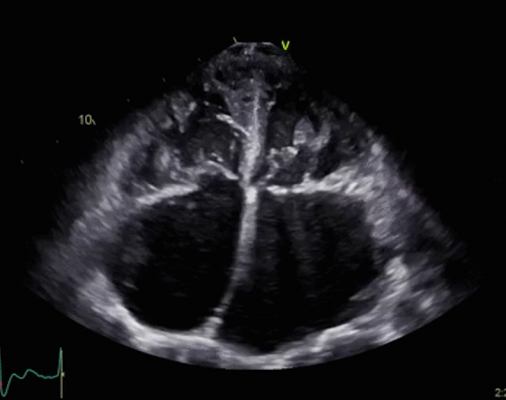

Physicians today need imaging studies that provide high-quality diagnostic capabilities no matter where the patient is, from the inpatient hospital setting to the outpatient and point of care settings. Bay Labs applies AI to cardiovascular imaging to help in the diagnosis and management of heart disease. An echocardiographic exam is the gateway to cardiovascular disease diagnosis and a key to disease management and appropriate timing of intervention. The company’s deep learning technology, a type of AI algorithm, is designed to help medical professionals of all skill levels perform and interpret echocardiograms and may improve the treatment of heart diseases. Bay Labs has partnered with the Minneapolis Heart Institute and Allina Health, Northwestern Medicine, Duke University School of Medicine and cardiologists at Stanford University to develop, test and validate deep learning algorithms for echocardiography.